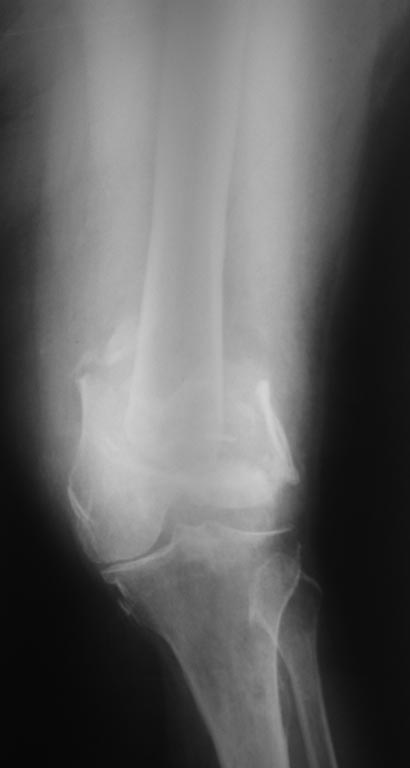

[Ortho] Перелом дистального отдела бедра

Перелом бедра у женщины 65 лет, случился 7 мес. назад( падение с высоты

роста на колено) . Живет в деревне, лечил хирург, снимки ни разу не делали.

Со слов больной после травмы в области коленного сустава была рана,

долго заживала.

Пациентка весит 120кг. В настоящее время передвигается в кресле коляске,

правая нога не опорная.Снимки и внешний вид конечности прилагаются

(свежие и единственные).

Из сопутствующей патологии: ожирение 3ст, артериальная гипертензия и

сахарный диабет 2тип, компенсация. Пациентка очень хочет самостоятельно

передвигаться.

Планируем выполнить артродез коленного сустава длинным штифтом(

бедро-голень). Хотелось услышать ваше предложения и мнения по тактике,

возможные варианты оперативного лечения.